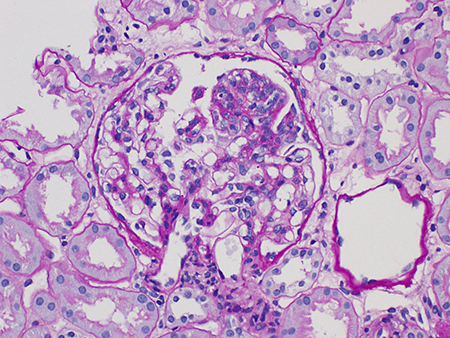

Mesangial hypercellularity (M0 or M1)[Figure caption and citation for the preceding image starts]: Mesangial hypercellularity in IgA nephropathy (Periodic acid-Schiff stain, x600)Courtesy of Drs Hwei Yee Lee, Cristine Ding, and Yong Howe Ho (Tan Tock Seng Hospital, Singapore) [Citation ends].